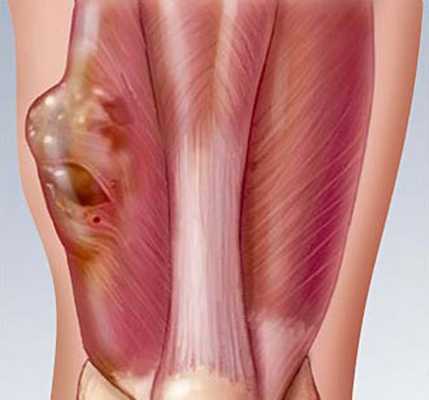

— Осмотр опытного специалиста, врача-онколога; На фото можно увидеть, как выглядит саркома мягких тканей:

— Рентгенологическое исследование. Позволяет визуализировать тень опухоли, деформацию прилежащих к опухоли фасциальных перемычек, выявить изменения в костях;